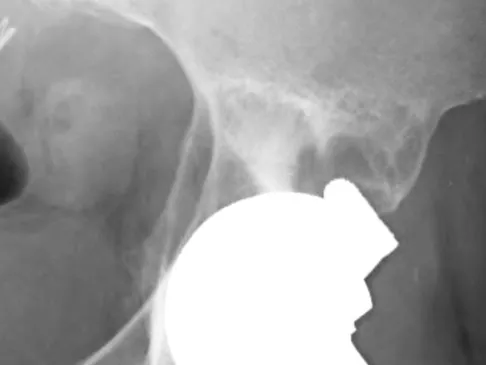

Figures 10a through 10c show the plain radiograph and MRI scans of a 41-year-old man who has right hip pain. What is the most likely diagnosis?

Explanation

Transient osteoporosis is a self-limited painful but reversible disorder. Although first described in pregnant women, it is more common in young to middle-aged men. The radiograph shows loss of mineralization in the right hip relative to the left side. There is no osseous destruction or cortical expansion typical of metastasis or giant cell tumor. The process is confined to the femoral side of the joint unlike rheumatoid arthritis, which would be centered in the joint. Osteonecrosis is better defined with sharp but irregularly shaped margins, and there is no double-line sign. The MRI scans reveal diffuse edema in the femoral head and neck that is atypical for osteonecrosis. Transient osteoporosis may recur in the same or opposite hip.